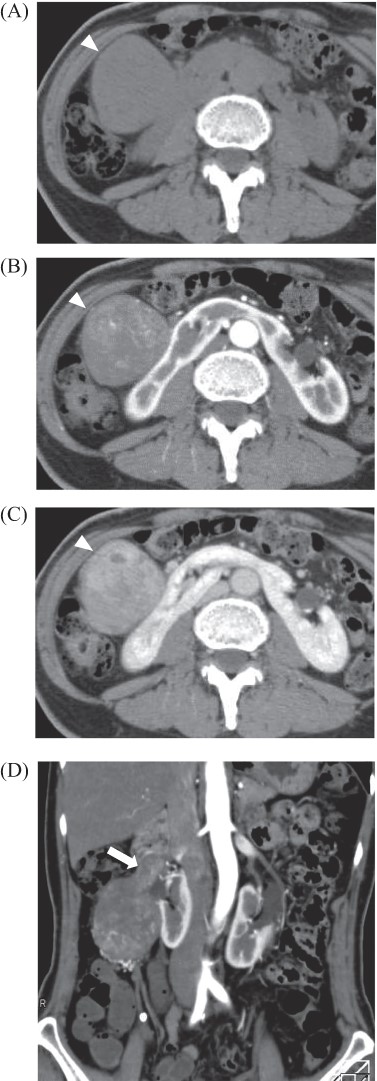

A 69-year-old woman presented to our institution with right abdominal pain. There was nothing special to mention in her family history. Her past medical history included horseshoe kidney, gastric ulcer, and asthma. Physical examination revealed a slight tenderness of the right quadrant abdomen. All laboratory parameters including the tumor markers carcinoembryonic antigen and carbohydrate antigen 19-9 were within normal limits. Abdominal ultrasonography showed a regularly shaped uniform tumor of about 50 mm in diameter that was located in the right retroperitoneum ventral to the right part of the horseshoe kidney. The tumor was hypervascularized (Fig. 1). Computed tomography (CT) showed a tumor of 80 mm in diameter ventral to the right part of the horseshoe kidney and the dorsal side of the descending part of the duodenum. On contrast-enhanced CT, the tumor showed late-phase enhancement. There were no findings of invasion into any organs and right ovarian vein ran through the tumor (Fig. 2). No metastases to organs or swollen lymph nodes were found. Magnetic resonance imaging (MRI) showed a tumor that was isointense with respect to muscle on T1-weighted images and of high-signal intensity on T2-weighted images (Fig. 3). No fatty components were detected in the tumor. Endoscopic ultrasonography showed a regularly shaped and hypoechoic tumor with no connection to the right part of the horseshoe kidney or duodenum (Fig. 4). Our working diagnosis was a retroperitoneal tumor that could be either a malignant lymphoma, leiomyoma or gastrointestinal stromal tumor.

Abdominal enhanced computed tomography: there was a tumor, 80 × 40 mm in diameter at the ventral side of the right kidney and dorsal side of the duodenum, which was enhanced in late phase (A: plane; B: arterial phase; C: late phase, arrowhead). Tumor located in the right ovarian vein and tumor thrombosis was detected (D, arrow).